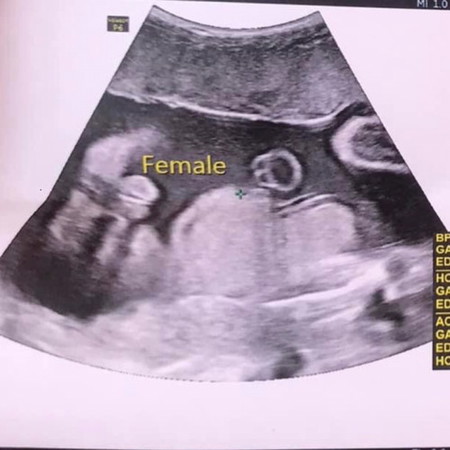

กังวลเล็กน้อยเรือเพศลูกค่ะ

ขอคนที่มีประสบการณ์ดูให้หน่อยค่ะ ว่ากรีบสาวจริงมั้ย หมอบอก100% แต่แอบกังวลเพราะกรีบใหญ่เหมือนไข่เลยค่ะ